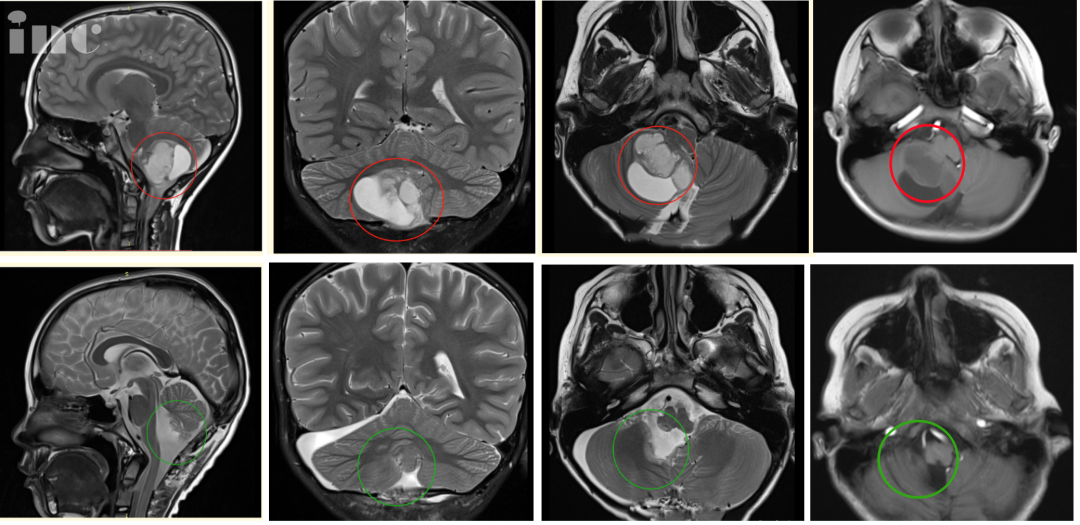

尽管此时的肿瘤已经达到40mm*37mm大小,且四脑室、脑干受压,中线结构局部左移,但辰辰并未表现出其他症状。要尽早手术吗?如果能安全切除肿瘤,辰辰父母也许不会如此纠结,偏偏肿瘤生长在小脑-脑干位置,不仅切除难度大,而且术后很可能会出现瘫痪、昏迷等并发症。

巴教授:“MR 显示非常典型的小脑良性肿瘤,常见的是毛细胞性星形细胞瘤。患儿需要手术。完全切除肿瘤后,这个患儿几乎可以从肿瘤中康复。切除率必须达到 100%,我将尽一切努力实现这一重要目标。”

“从我们到达德国之后,一直到小孩进手术室,我心里对巴教授的信任基本是百分比的。”最终,辰辰的手术十分成功,肿瘤得到全切,脑干充分减压,对中脑的挤压/移位压力明显减少,小脑也复位了。术后病理结果为毛细胞型星形细胞瘤,WHO 1级,这代表着只要全切,辰辰的预后将很好,甚至有望达到长期生存的治愈性结局。